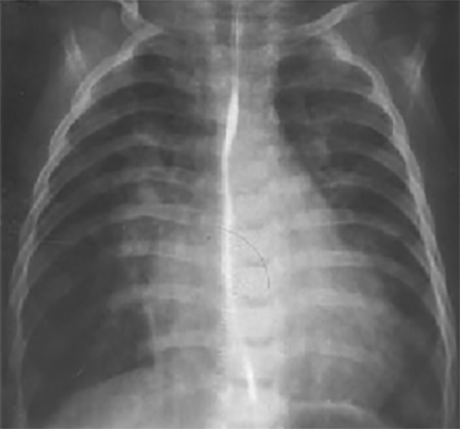

Another Patient

PA and Lateral

Click on the xrays to enlarge them.

Choose the best interpretation of the chest X rays:

RV enlargement, dilated

pulmonary trunk, increased pulmonary

arterial vascularity

LA/biventricular enlargement,increased pulmonary arterialvascularity

LV enlargement, aortic dilatation

RV hypertrophy, smallpulmonary trunk, decreasedpulmonary arterialvascularity

Dilated pulmonary trunk, normal vascularity